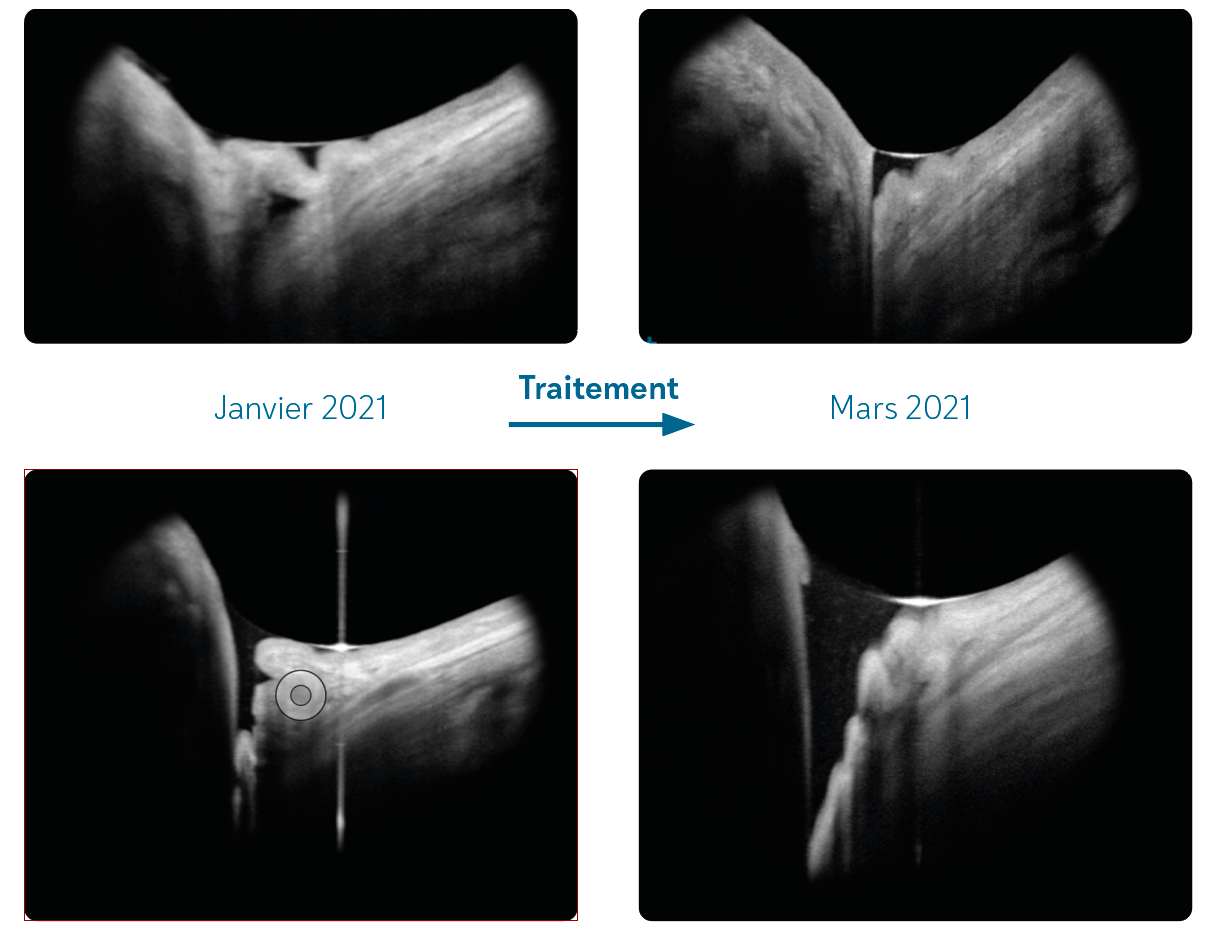

Figure 5. À gauche : Schisis du myope fort avec menace de trou maculaire. Au milieu : J7 postchirurgie avec Foveal Sparing. À droite : M10 postchirurgie.